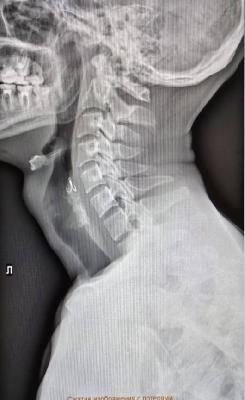

Во время рыбалки мужчина держал во рту наживку, и когда лодку качнуло, случайно проглотил её.С острой болью он обратился в больницу, где врачи на рентгене обнаружили крючок, застрявший в глотке.

Медики краевой больницы извлекли приманку с помощью эндоскопа. Сейчас с рыбаком всё в порядке.